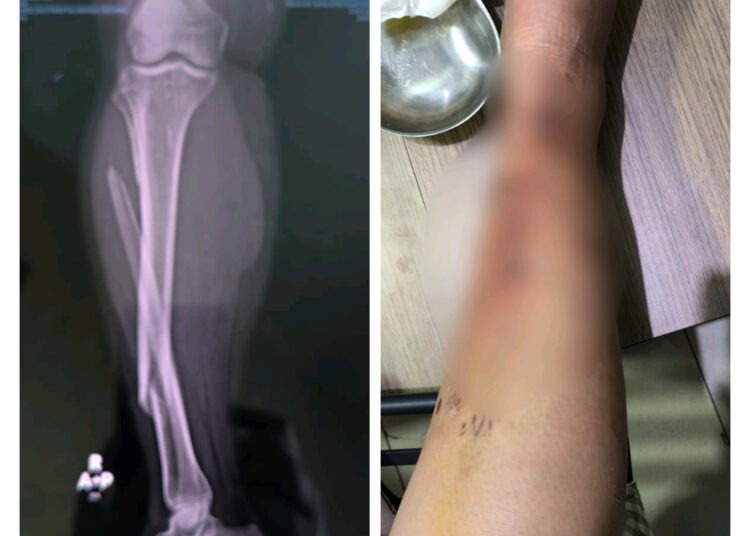

Korban pun terlempar dari kendaraan nya dan jatuh kekiri jalan dengan posisi terduduk. Saat hendak berpindah, korban merasakan kakinya tak lagi bisa digerakkan.

“Langsung ramai warga disitu. Saya juga merasa kaki saya sudah gak bisa gerak sebelah kanan, saya sudah merasa ini patah jadi saya gak mau sembarangan diangkat,” ujarnya.

Sejumlah warga hendak membantu, namun Eko menyampaikan bahwa kaki sebelah kanannya terasa nyeri hebat, sehingga ia menolak untuk diangkat sebelum bantuan medis tiba dilokasi kejadian.

“Kakinya patah dan harus di pen, kurang lebih empat hari dirawat dan sekarang masih harus rawat jalan empat kali seminggu kontrol,” terang Digdo.